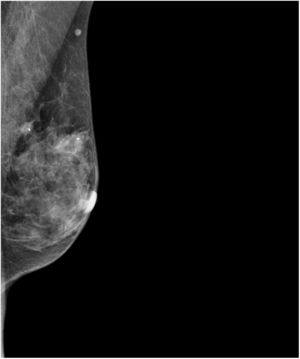

Acudió al servicio de radiología de nuestro centro derivada por su médico de atención primaria por notarse un bulto de aproximadamente 2cm en el cuadrante superior interno de la mama izquierda. Siguiendo el protocolo de nuestro centro, se realizó mamografía, ecografía y mamografía con contraste (fig. 1). En esta última se visualizó una lesión nodular de 17×17mm con pequeñas microcalcificaciones en su interior y con marcado realce, que tras la inyección de contraste se clasificó como BIRADS5 (fig. 2). En la ecografía complementaria se visualizó, además de dicho nódulo, otro de aspecto sospechoso, de 9mm, localizado más internamente. Se realizó BAG ecoguiada del primer nódulo con la siguiente histología: carcinoma mucosecretor G1, RE+++, RP++, Ki67 10%, HER2-positivo. La axila era clínica y ecográficamente negativa. El estudio de extensión no evidenció afectación ganglionar. Se estadificó como cT1c-N0cMx.

El diagnóstico radiológico de los CMS no difiere del resto de cánceres invasivos de mama. Pueden simular lesiones de aspecto benigno, pero en la mayoría de las ocasiones se detectan por mamografía como masas ovaladas con márgenes microlobulados4. Se ha descrito en la literatura una posible relación entre el aspecto radiológico de las lesiones y la cantidad de mucina que poseen los CMS4. No obstante, no existe suficiente correlación para poder diferenciar radiológicamente los tipos de CMS.